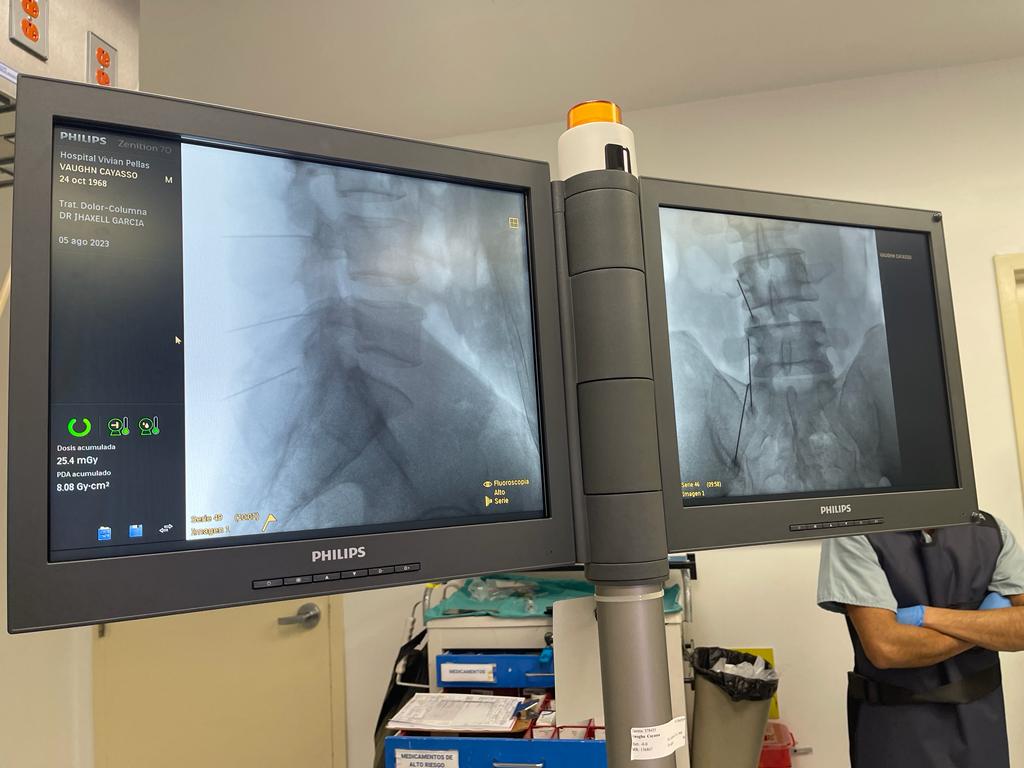

Rizólisis (Ablación por Radiofrecuencia)

Técnica mínimamente invasiva para tratar el dolor crónico articular de la columna

¿Qué es?

La rizólisis es un procedimiento no quirúrgico que utiliza energía de radiofrecuencia para inactivar de forma selectiva los nervios responsables de transmitir dolor desde las articulaciones facetarias de la columna.

¿Para quién está indicada?

- Pacientes con dolor lumbar o cervical crónico, de origen mecánico

- Artrosis o degeneración de las articulaciones facetarias

- Dolor que no responde a tratamiento conservador (analgésicos, fisioterapia, bloqueos)

- Personas que no son candidatas a cirugía mayor

Beneficios

- Procedimiento ambulatorio

- Bajo riesgo de complicaciones

- Mejora del dolor durante meses (en ocasiones más de un año)

- Puede repetirse si reaparecen los síntomas